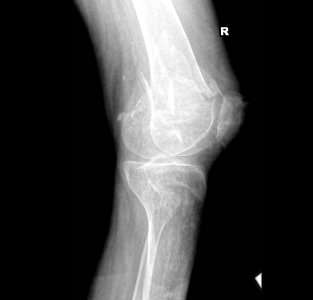

Случился "вколоченный осколочный, косой внесуставной перелом нижней трети диафиза правой бедр. кости с незначительным заходом осколков без признаков консолидации" а так 1.jpg2.jpgже "осколочный внутрисуставной перелом основы правого надколенника без смещения, без признаков консолидации"(снимки

http://fastpic.ru/view/59/2013/1022/81096fc26fcb57d606ecc6ce5a2f254d.jpg.html). Врачи в связи с тем, что у меня нижняя параплегия ограничились наложением лангеты на коленный сустав часть голени и часть бедра. Интересует следующее: как повлияет укорочение ноги в связи с этим переломом на процесс реабилитации и вероятного прямохождения (надеюсь что буду ходить), насколько она станет короче (можно ли судить по снимкам) и каковы есть решения проблемы неравности ног? Насколько целесообразно делать операцию и укреплять перелом пластинами и т.д. в моем положении на фоне остеопороза?